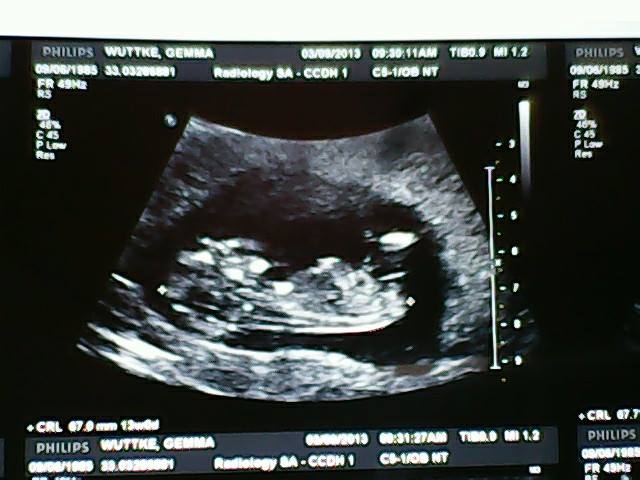

Attachment 14020Attachment 14021Attachment 14022

Boy!

The angle looks like boy.

I'm 50/50 on this one.....the nub is really long but it's on a slight angle, but I'm not too sure if it's because of the position of bubs! Congrats on a cute baby :)

ty ladies i have no idea :)

I think girl. It's long and it's angle just isn't enough to convince me on boy for gestation. I think a boy would be much greater in angle. Good luck!

Girl

I would guess girl. It looks really similar to my DD at 13 weeks.

Leaning pink.